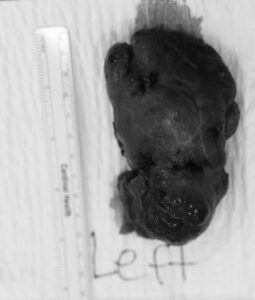

សម្តេចមហាបវរធិបតី ហ៊ុន ម៉ាណែត» និង «លោកជំទាវបណ្ឌិត ពេជ ចន្ទមុន្នី ហ៊ុនម៉ាណែត» តែងមានចិត្តសណ្តោសប្រណី និងក្តីមេត្តាករុណាដ៏ខ្ពង់ខ្ពស់បំផុតចំពោះប្រជាជនគ្រប់ៗគ្នា ឆ្លុះបញ្ចាំងតាមរយៈការអនុញ្ញាតឱ្យក្រុមគ្រូពេទ្យ នៃសមាគមគ្រូពេទ្យស្ម័គ្រចិត្តយុវជនសម្តេចតេជោ TYDA នាំ អ្នកមីង “សម រដ្ឋា” អាយុ ៥៨ឆ្នាំ រស់នៅសង្កាត់ចោមចៅទី៣ ខណ្ឌពោធិ៍សែនជ័យ រាជធានីភ្នំពេញ មកទទួលការព្យាបាលវះកាត់ដុំសាច់ពកកផ្នែកខាងឆ្វេង ដោយក្រុមគ្រូពេទ្យស្ម័គ្រចិត្តវះកាត់ផ្នែកជំងឺទូទៅមកពីសហរដ្ឋអាមេរិក នៅមន្ទីរសម្រាកព្យាបាលក្តីសង្ឃឹមនៃយេរេមា (JHMC) នៅថ្ងៃទី២៦ ខែសីហា ឆ្នាំ២០២៥ ។